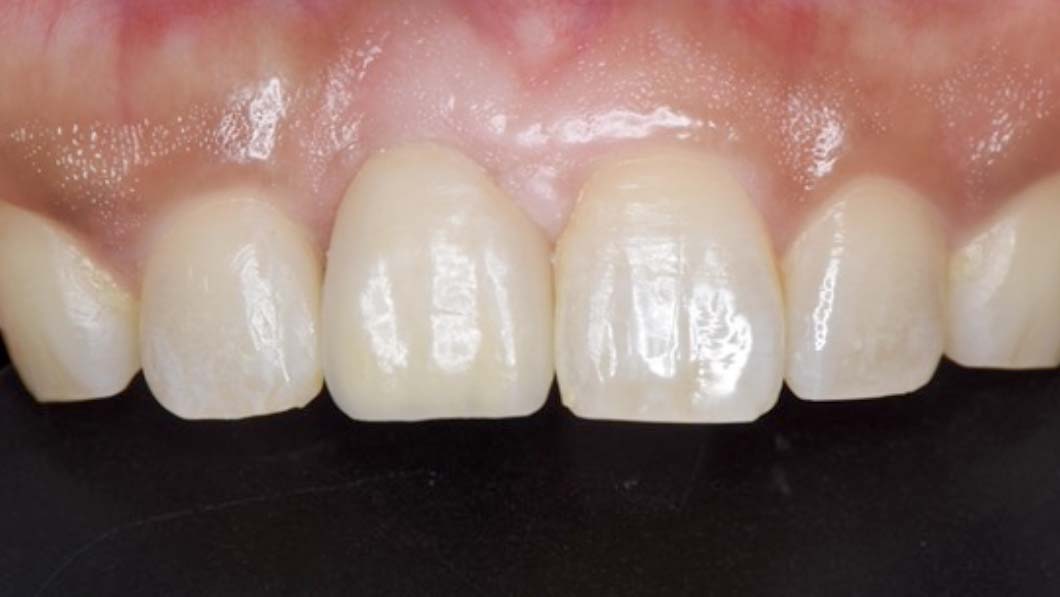

- 右上1を抜歯しソケットプリザーベーション(抜歯したまま放置すると骨が高度に吸収してしまうため、それを予防するための処置)を行い、隣在歯と骨レベルを合わせたのちにインプラント埋入を行った。

インプラントは理想的な状態に仕上がり、他の歯のクラウンも美しく調和することができた。患者さんも非常に満足度がたかかった。